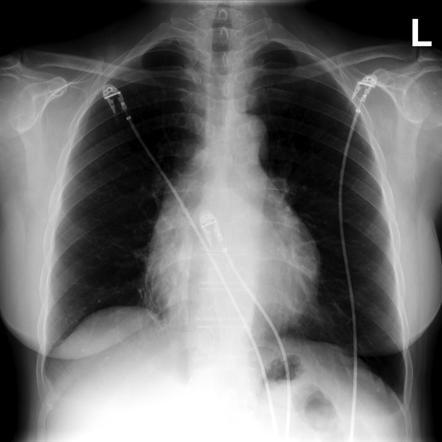

Pericarditis investigations CXR?

may be globular if there’s pericardial effusion